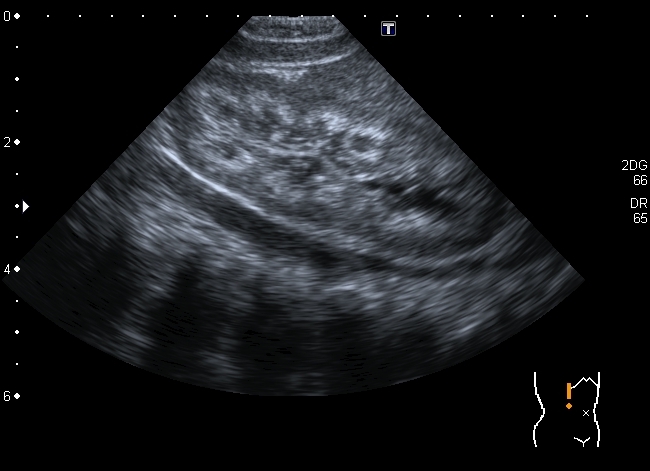

Ребёнок 1-го месяца, оперирован по поводу ВПС, транспозиции магистральных сосудов. В послеопреационном периоде сепсис. Сейчас пришли для обследования перед направлением на МРЭК

Почка Андерсона-Карра. По периферии пирамид определяются эхогенные «кольца» из-за накопления там депозитов кальция.

У детей наиболее частой причиной нефрокальциноза является первичный тубулярный ацидоз и первичная гипероксалурия.